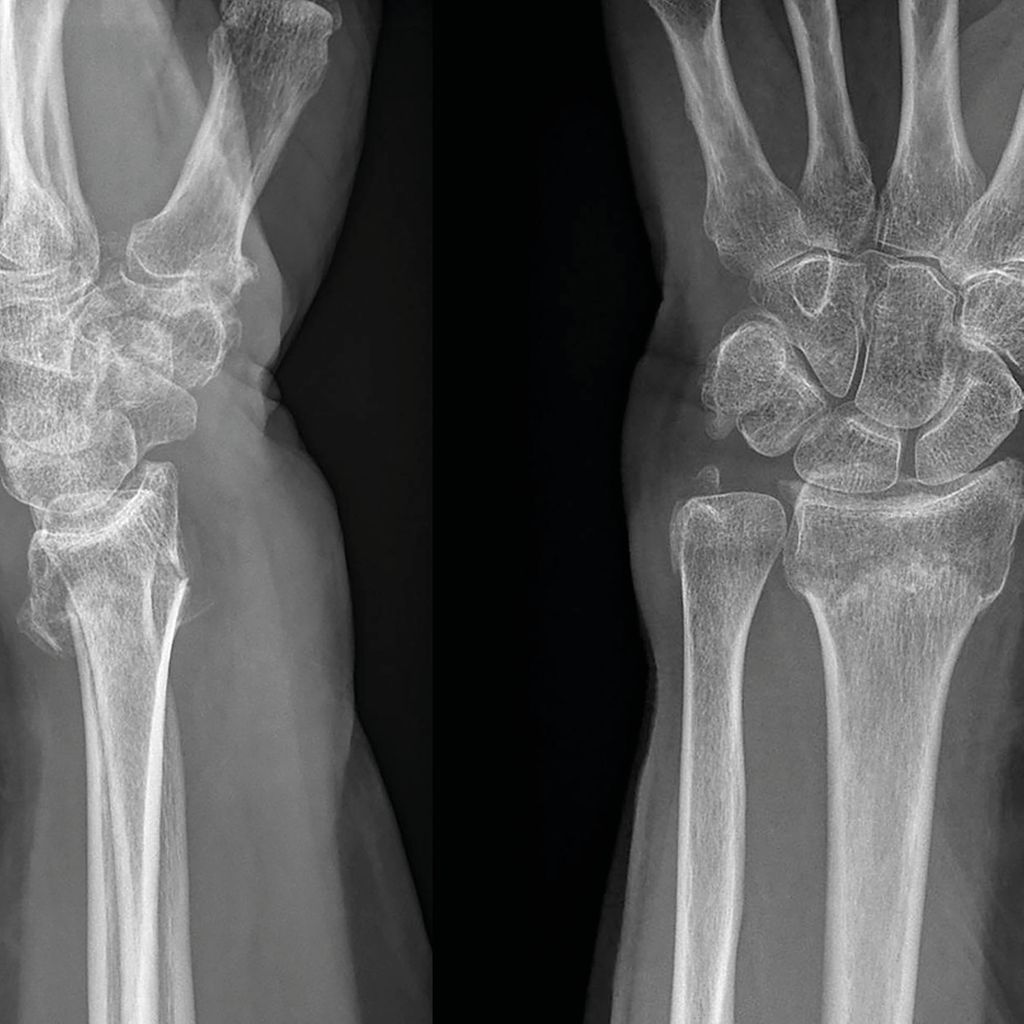

Nach Radiusfraktur Schmerzen Im Daumen . 4 Übungen nach einem Speichenbruch (Radiusfraktur) Sarah Daurer YouTube Die Komplikationsrate nach distaler Radius-fraktur wird in der Literatur sehr va- Die Finger und das Handgelenk sind geschwollen, mein Gelenk fühlt sich an, wie im Schraubstock

Schmerzen im Daumen nach Radiusfraktur Yoga zur Stärkung nach Handgelenksbruch DajaYoga . Die Komplikationsrate nach distaler Radius-fraktur wird in der Literatur sehr va- Folgen einer Radiusfraktur - FOCUS online Themen Services Login